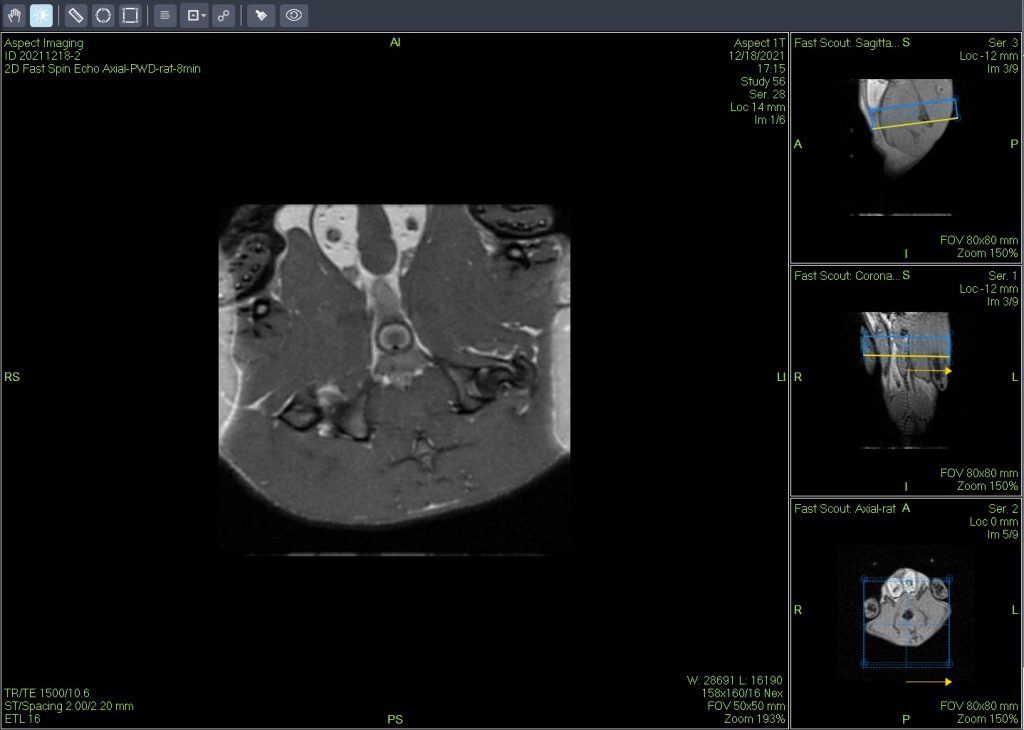

一个新的紧凑型高性能小动物磁共振成像平台(M3),该系统使用一种新的磁铁设计和一套相关的软件,降低了小动物磁共振成像仪的成本和复杂性。

Dixon脂肪抑制技术是由Dixon 提出,其基本原理是利用水、脂肪的化学位移差异,使用不同的回波时问,分别采集水和脂肪质子的in Phase 和 opposed -phase两种回波信号。